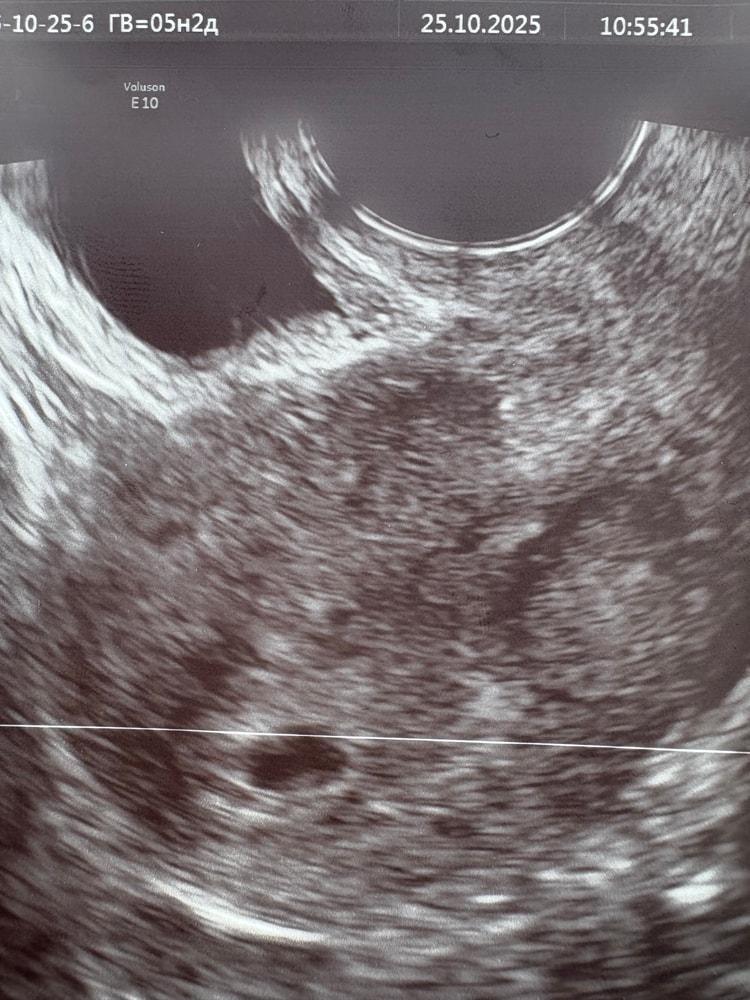

19 дпп, акушерский срок 5 недель 2 дня

Результаты УЗИМое беременное узи! 😍🥰 Плодное яйцо 6,2 мм, даже увидели желточный мешочек 2,1 мм. Сказали все соответствует сроку, повторить узи через 1-2 недели, чтобы послушать сердечко ♥️